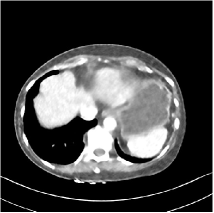

Refer to caption WavResNet [11]Refer to caption WavResNet [11]Refer to caption WavResNet [11]Refer to caption Momentum-Net (SimpleCNN)Refer to caption Momentum-Net (SimpleCNN)Refer to caption Momentum-Net (SimpleCNN)Refer to caption Momentum-Net (SimpleCNN-RSN)Refer to caption Momentum-Net (SimpleCNN-RSN)Refer to caption Momentum-Net (SimpleCNN-RSN)Refer to caption Momentum-Net (Dn-RSN)Refer to caption Momentum-Net (Dn-RSN)Refer to caption Momentum-Net (Dn-RSN)Refer to caption ReferenceRefer to caption ReferenceRefer to caption Reference

Fig. 3: Three examples (from top to bottom) of the reconstructed testing images using Momentum-Net with SimpleCNN (the second column), with SimpleCNN-RSN (the third column), and with Dn-RSN (the fourth column). The compared WavResNet denoised images are shown in the first column, and the reference images are in the fifth column. See their FBP images in Fig. 4.

Fig. 2 shows that the proposed Momentum-Net with SimpleCNN decreases RMSE dramatically in the first 30 layers, and tends to converge in 50 layers. The Momentum-Net reduces the mean RMSE value by 4.5 HU and gives smaller standard deviations in RMSE, compared to WavResNet, as reported in Table 1. This implies that the proposed Momentum-Net with SimpleCNN can improve both the accuracy and stability of low-dose CT image reconstruction than a state-of-the-art image denoising deep NN, WavResNet. The proposed Momentum-Net with SimpleCNN better removes noise and streak artifacts than WavResNet. It also provides clearer reconstructions of some details; see, in Fig. 3, the boundaries shown in the zoomed region at the top-right corner in the first example, the arrow pointed structures in zoomed areas of the second example, and the arrow pointed tissues in the left zoomed region in the third example.

3.3 Momentum-Nets involving RSN-based training